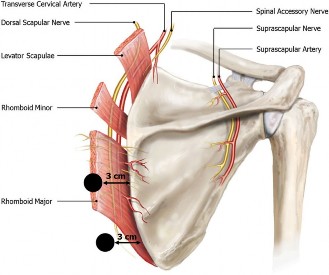

The correct answer is (A). In young, active patients with a massive, irreparable rotator cuff tear without glenohumeral arthritis, a tendon transfer is the most reasonable option to attempt to restore function of the shoulder. In a tear involving the supraspinatus and infraspinatus, the posterior and inferior force-couples in the transaxial and coronal planes, respectively, are out of balance because of the involvement of the infraspinatus in both of those. Because of this, the humerus cannot be dynamically stabilized in the glenoid during active movement of the shoulder. The most popular way to restore this in a young, healthy patient is through a latissimus dorsi tendon transfer in which the insertion of the tendon is transferred from the humeral shaft to the greater tuberosity (see Fig. 2–19). This creates a new posterior and inferior force-couple and creates an external rotation force.

Figure 2–19_Latissimus dorsi tendon transfer on a right shoulder viewed from superiorly with anterior being the left side of the image. Top: final appearance. Bottom: final sutures being thrown through the latissimus dorsi. (From Omid R, Lee B. Tendon transfers for irreparable rotator cuff tears. _J Am Acad Orthop Surg. 2013;21(8):492–501.)

It should be noted that due to the differences in the length and force vector magnitude and direction between the infraspinatus and latissimus dorsi, the force couple is not perfectly restored, and thus the shoulder after a tendon transfer never works as well as with a successful repair of the native cuff. The latissimus force vector is much more vertical and greater in magnitude than the infraspinatus. This transfer thus has variable results in restoring function. Factors associated with poor outcome include subscapularis dysfunction, deltoid dysfunction, osteoarthritis of the glenohumeral or acromioclavicular joint, and loss of teres minor function, none of which are present in this patient.